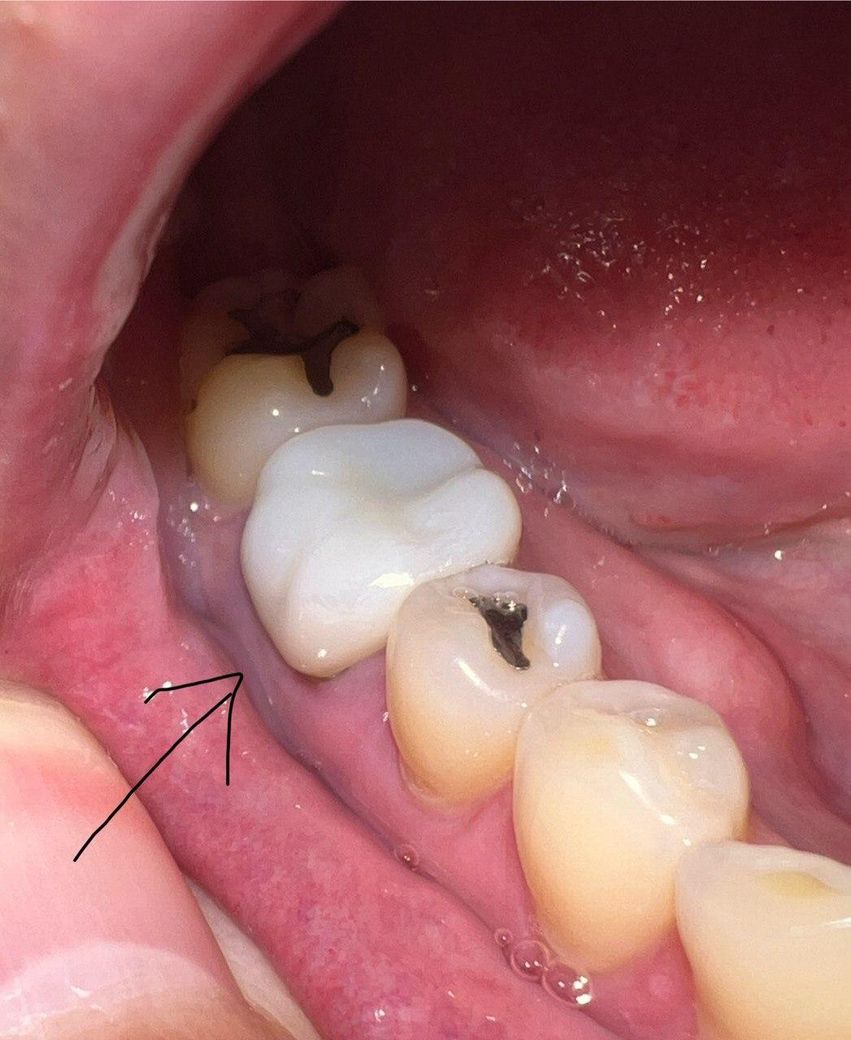

약 5년전 어금니에 크라운을 씌웠는데

오늘 우연히 거울을 보니 아래 사진처럼 잇몸이 살짝 녹아서(?) 내부 치아가 드러나있는걸 발견했습니다.

다행히 시리거나, 통증이 있거나, 크라운이 흔들리거나, 피가 나는 등의 문제는 없습니다.

보철치료를 하고 난다음 경계부위가 내려가면서 보철물의 경계가 보일수 있습니다. 크게 문제가 되지는 않지만 심미적으로 신경이 쓰인다면 보철치료를 다시 받는 것이 좋을수 있습니다.

나이가 들면서 잇몸이 퇴축되면서 치아의 뿌리가 약간 노출된거 같습니다. 일단은 관리를 하시면서 사용하셔도 될것같습니다.

간혹 시간이 지남에 따라 저렇게 잇몸이 내려가긴 하지만 주위 잇몸 상태가 건강한 것으로 보아 병적인 상태는 아니니 걱정하지 않으셔도 되겠습니다.